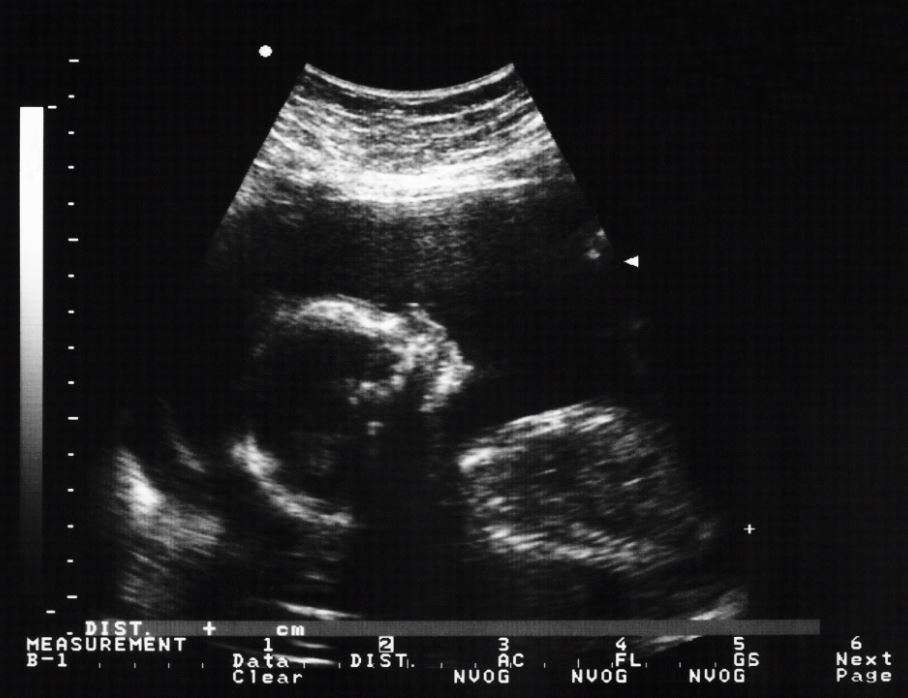

To do this, first an ultrasound is done to locate the embryo in the uterus. After about twenty milliliters will be extracted, that is, a little liquid. Local anesthesia is not used in this procedure, although a cream can be used to numb the area.

The fluid is obtained through a puncture with a fine needle that is inserted through the abdominal wall and the uterus. While the puncture is being performed, an ultrasound is performed so that the extraction of the liquid is correct. This procedure usually lasts 20-30 minutes and you may feel a sting or pressure during the test, although you may not feel any pain.